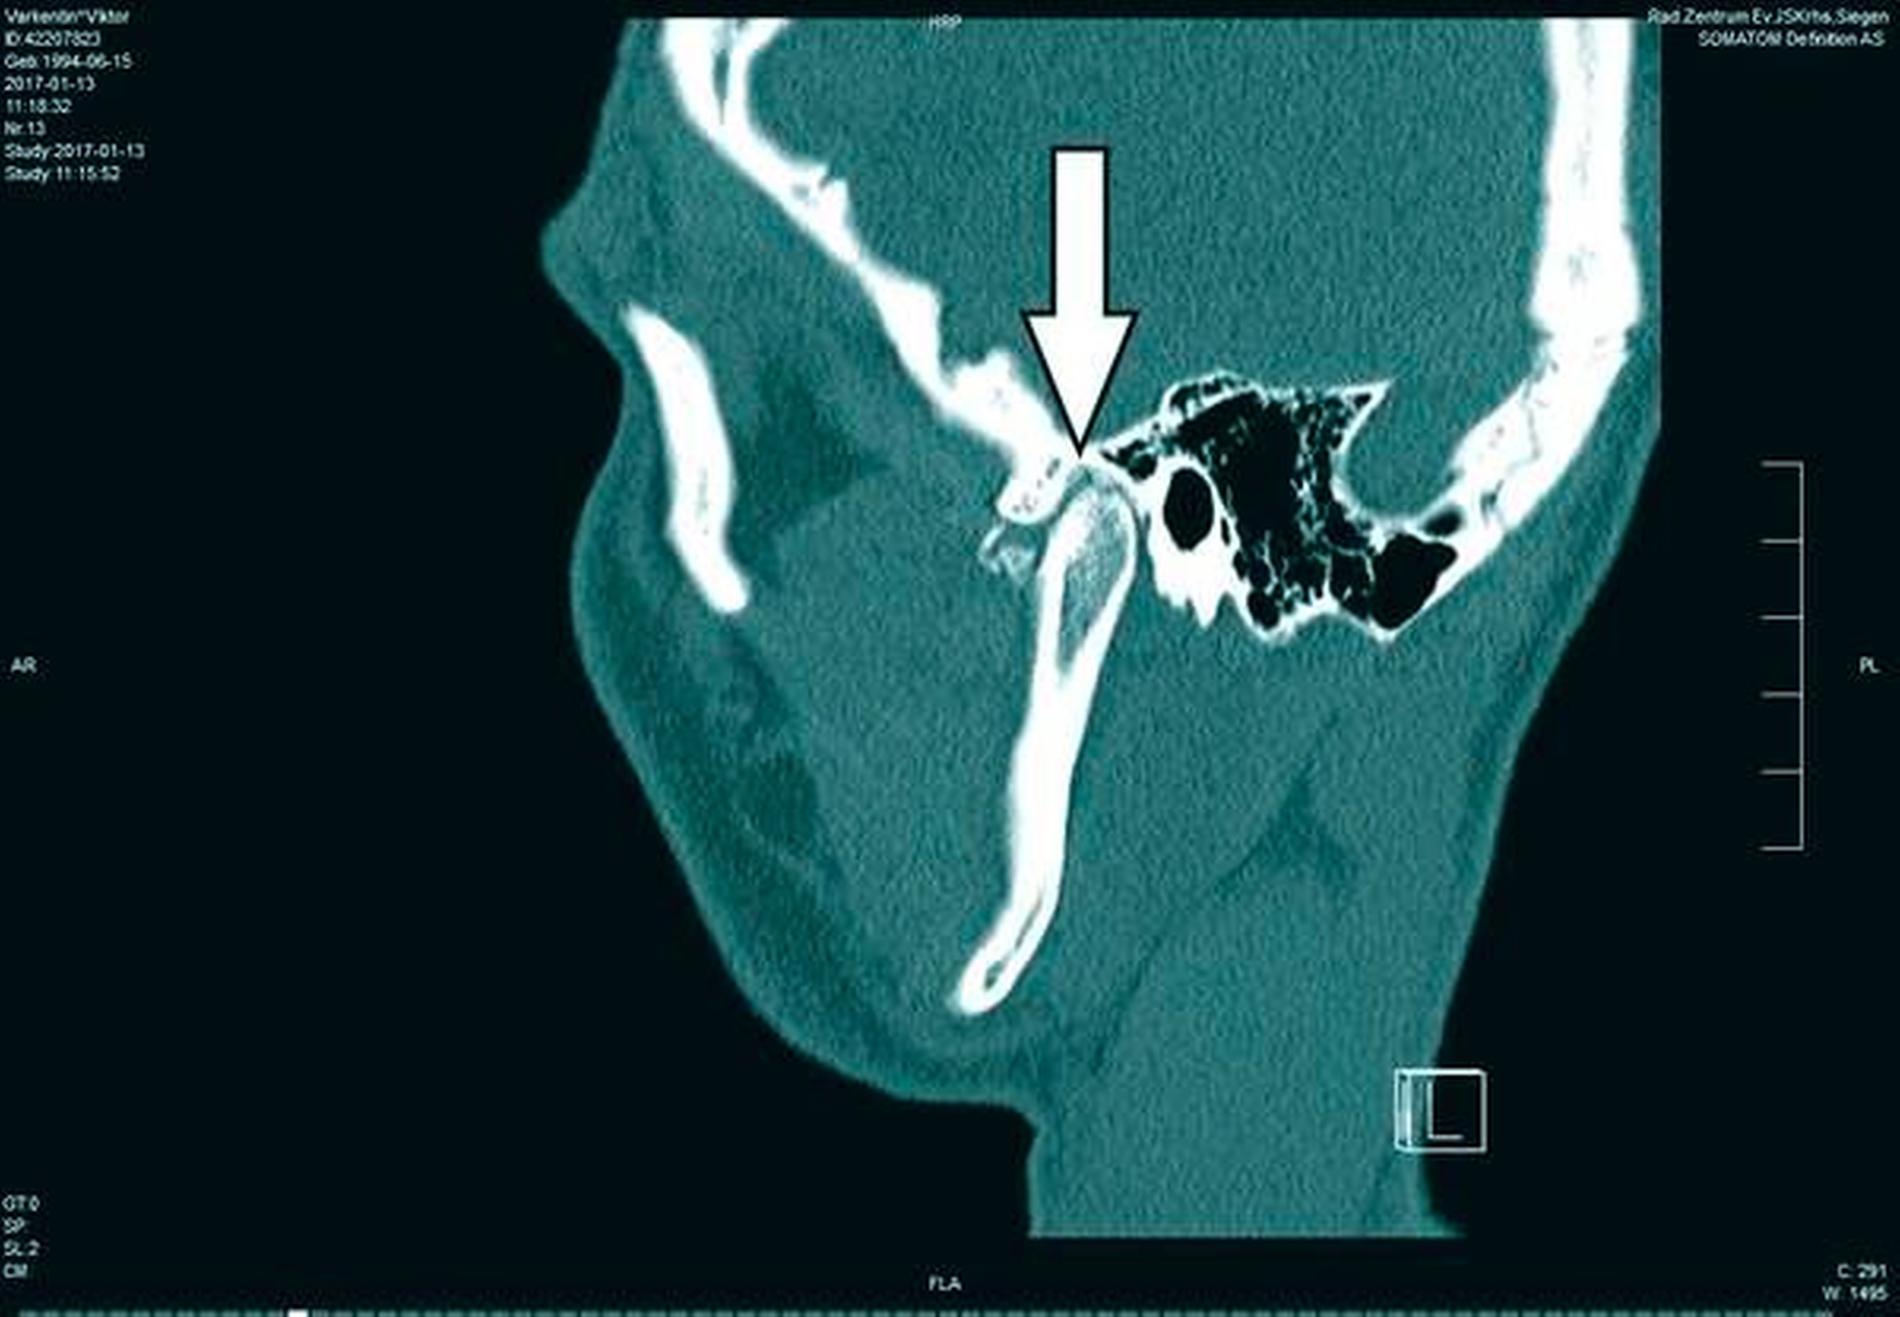

In der Folge entwickelte sich binnen fünf Monaten eine absolute Mundöffnungsbehinderung. Die SKD betrug null Millimeter. Passend zur klinischen Symptomatik zeigten sich radiologisch die Zeichen einer knöchernen Ankylose der Kiefergelenke beidseits Typ III nach Sawhney [1986] (Abbildung 1a bis 1d).